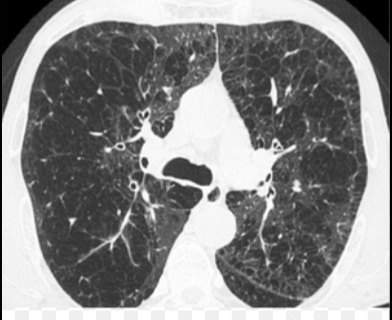

Que imagen distingue distribución en EPOC enfisematoso?

TC

Paraseptal